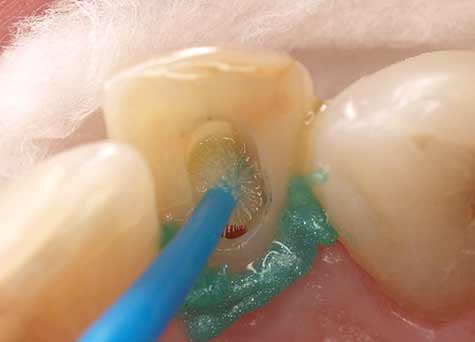

Het gebruik van Futurabond U in de Self-Etch-techniek is zinvol in klinische casussen waarbij alleen de dentinesubstantie hoeft te worden geëtst en/of het glazuurgebied geen intensieve en zeer agressieve conditionering nodig heeft. Aan de hand van de klinische casus van een 42-jarige patiënt worden de bevestiging van een stift en het gebruik van Futurabond U na een zeer ruime caviteitpreparatie voor een prothetische restauratie getoond, waarbij grotendeels alleen dentine werd geëtst. Door speciale applicators (Endo Tim, VOCO) voor gebruik in het wortelkanaal kan het adhesief ook daar zijn volledige werking ontwikkelen, omdat een volledige bevochtiging van de kanaalwanden plaatsvindt. Het actief inmasseren van Futurabond U in alle dentine-oppervlakken in het wortelkanaal bereidt de tandstructuur optimaal voor de aansluitende bevestiging voor (afb. 4-6). Een in het wortelkanaal lastig uit te voeren uitharding met licht is bij het duaalhardende Futurabond U niet nodig.

Afb. 4: Applicatie van Futurabond U in kanaalingang

Afb. 5: Met de speciale applicator EndoTim (VOCO) wordt het wortelkanaal betrouwbaar bevochtigd met Futurabond U